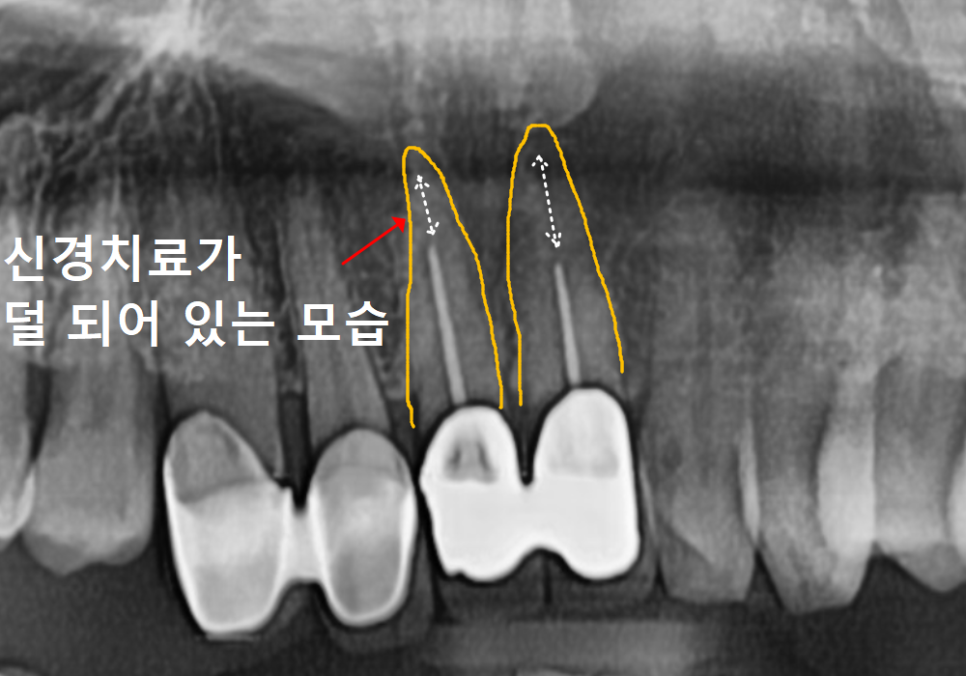

무엇보다 "씹을 때 욱신거린다"는

통증을 호소하셨는데,

정밀 검사 결과 ,

과거 신경치료가 제대로 마무리되지 않아

내부에 염증이 생겨 있었습니다.

230215

기존 치료가 불충분했다면

신경관이 막혀 있거나

방향이 뒤틀려 있을 수 있어,

원래의 길을 다시 찾아내는 게

정말 쉽지 않습니다.

230424

이번 환자분 역시 신경이

뿌리 끝까지 제거되지 않은 상태였지만,

다행히 숨은 길을 잘 찾아내어

3번의 꼼꼼한 소독 끝에

안전하게 치료를 마무리할 수 있었습니다.